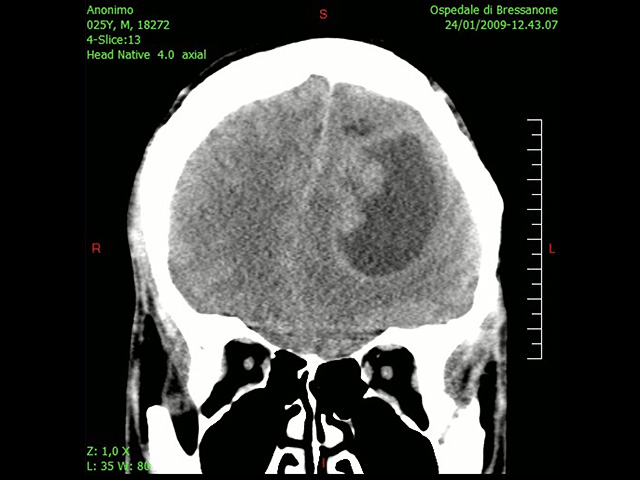

Менее 5% пациентов с диагнозом глиобластома живут 5 лет и дольше, поэтому борьба с этим онкологическим заболеванием является одним из важных приоритетов ученых. Мозг долгое время считался стерильной средой, защищенной гематоэнцефалическим барьером от проникновения патогенов. Но новое исследование показало, что различные бактерии успешно преодолевают эту защиту и обитают внутри опухолей мозга. Работа опубликована в журнале Nature Cancer.

Ученые проанализировали 322 образца глиобластом и метастазов в мозге. Исследователи обнаружили бактерии как внутри опухолей, так и среди окружающих опухоль иммунных клеток. Метастазы оказались даже богаче бактериями, чем первичные опухоли – они содержали большее количество и разнообразие микроорганизмов.